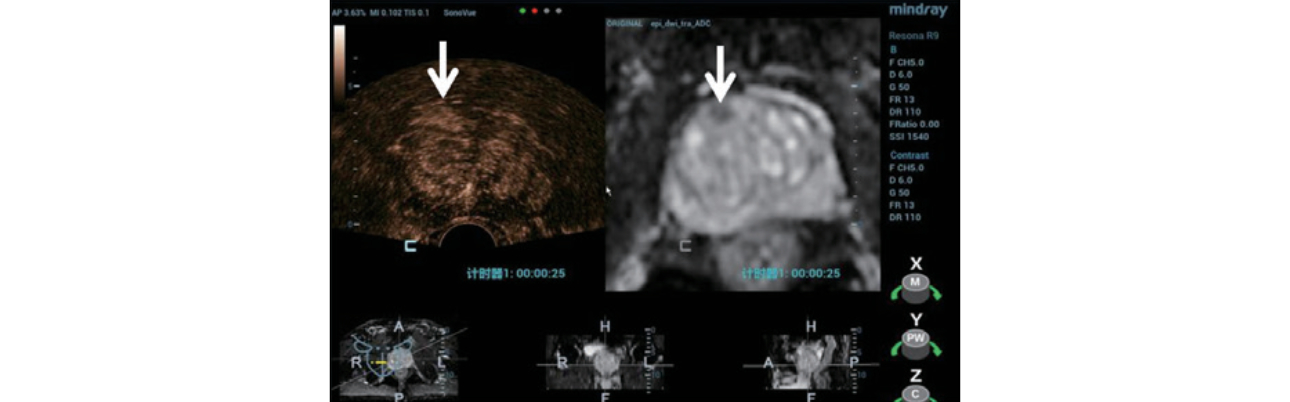

TRUS/MRI ?? ?? ?? ??:

Step 1:???? MRI sequence(Figure 2) ?? ? Resona 9? ??? ??? ??? ??? ??? import ?????.

Step 2:??????? iFusion ?????? ???? TRUS/MRI ???? ?? ? ??(Figure 3) ?? ?? ???(Figure 4).